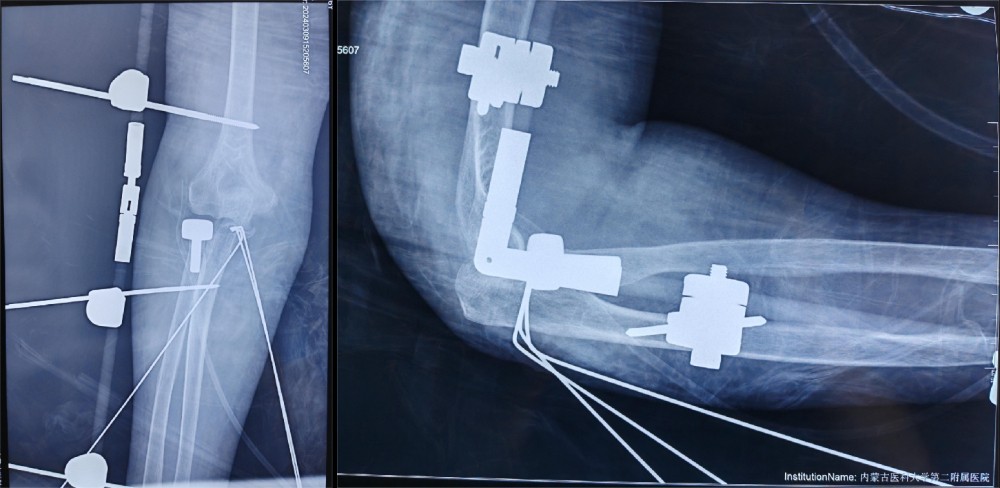

结合患者年龄及损伤类型,按照肘关节恐怖三联征的标准化治疗理念,副院长冯卫教授、创伤外科中心A区团队与李庭教授充分沟通、讨论后,由李庭教授及冯卫教授团队共同为患者施行标准化的治疗:“单一肘关节外侧切口,进行右冠状突骨折切开复位内固定术,右桡骨头粉碎性骨折桡骨头置换术,右肘关节外侧副韧带修复术,术中见右肘关节仍不稳定,随后给予右肘关节外固定架固定术”。标准化的治疗流程,使得这位高龄患者达到了与北京积水潭医院同质化的治疗。

以医院高质量发展为契机,依靠京蒙协作平台,北京积水潭医院著名创伤骨科专家李庭教授,作为我院外聘教授,高度重视我院创伤急救外科学科建设,从繁忙的日程中抽出宝贵时间,亲临我院进行复杂肘关节损伤的教学手术。整个手术过程行云流水,从细致的术前准备,到精确的手术操作,再到细致的术后管理,体现出李庭教授极高的专业水准和精益求精的手术理念。